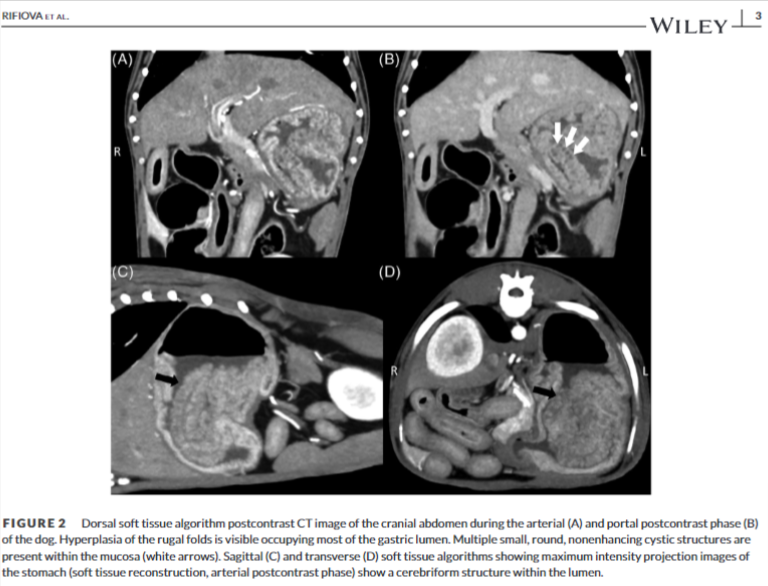

| 메네트리에 유사 질환(Ménétrier-like disease, MLD)은 개에서 매우 드물게 발생하는 위 질환으로, 사람의 메네트리에 질환과 유사한 특징을 보입니다. 이 질환은 위 점막의 비대와 낭포성 변화를 특징으로 하며, 주로 노령견에서 발생합니다. 주요 증상으로는 식욕 부진, 체중 감소, 구토 등이 있으며, 심한 경우 저알부민혈증이나 단백질 소실성 장병증이 나타날 수도 있습니다. 진단은 주로 영상 검사와 조직 검사를 통해 이루어집니다. 복부 초음파에서는 위벽이 두꺼워지고, 점막이 비대해져 주름이 위 내강으로 돌출되어 있는 모습을 관찰할 수 있습니다. 또한, CT 검사에서는 뇌회 모양의 위 점막 주름이 특징적으로 나타납니다. 조직 검사를 통해 foveolar hyperplasia, lamina propria의 샘 비대, 낭포성 확장 등을 확인하여 확진할 수 있습니다. 치료는 아직까지 명확하게 확립된 방법은 없지만, 증상 완화를 위해 약물 치료나 수술적 치료를 시도할 수 있습니다. MLD는 예후가 좋지 않은 질환으로 알려져 있으며, 적절한 치료에도 불구하고 사망에 이를 수 있습니다. 따라서 조기에 진단하여 적극적으로 치료하는 것이 중요합니다. |

CT 영상도 거의 초음파 영상과 유사한 양상을 보인다.